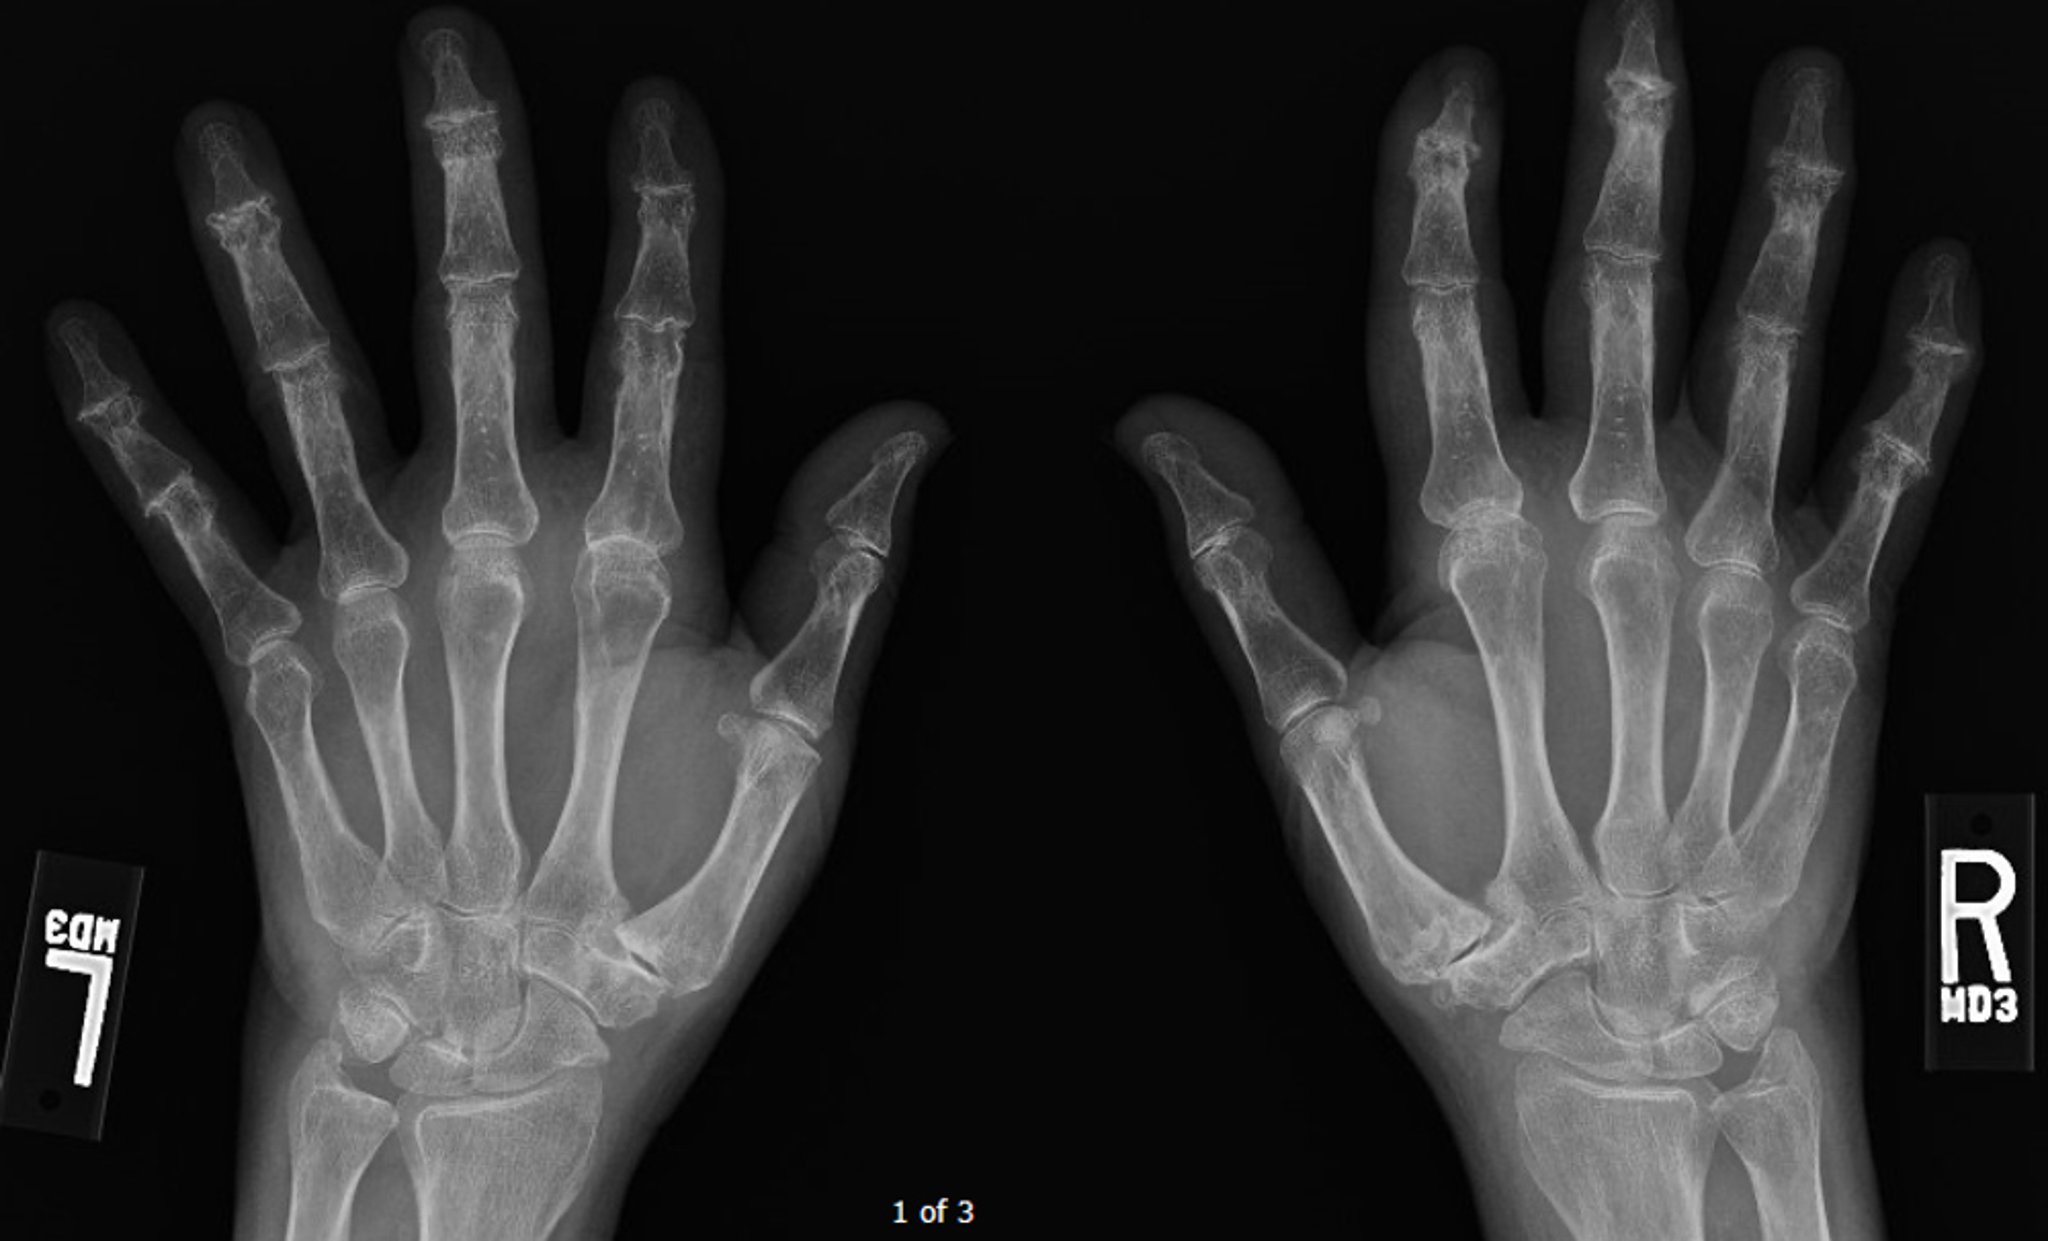

Arthrose érosive

Cette radiographie montre une arthrose diffuse avancée, en particulier au niveau des articulations interphalangiennes distales, où quelques érosions centrales peuvent être observées.

Image courtoisie de Kinanah Yaseen, MD.